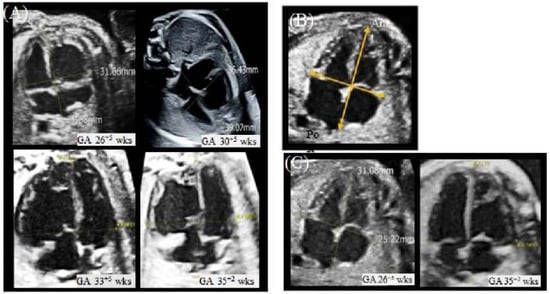

At a GA of 35+2 weeks, the globular RV of the upper fetus persisted (Figure 2A). Because a rare cardiac chamber disease was suspected, a decision to consult a pediatric cardiologist was made. After consultation, right-sided ventricular diverticulum was diagnosed. Although the outpouching portion of the ventricular wall was observed to be wider than previously reported, ventricular diverticulum was diagnosed because of the synchronous contraction of the wall and the intact thickness of the ventricle. The evaluation of ventricular thickness and synchronous contraction was assisted by the analysis of the acquired STIC volume. Cardiac images with STIC more markedly indicated these muscle layers than B-mode images, and synchronous coordination was more clearly observed in the video of the cardiac cycle with STIC (Figure 2B,C, Supplementary Video S1).

Since the new ultrasound device, a Voluson E10 with an eM6C G2 metrix probe (GE Healthcare Korea, Seoul, Korea), had been introduced to our hospital, quantitative assessment of the fetal heart using FetalHQ was performed. First, in the four-chamber view (4CV) global size and shape, the global sphericity index (GSI) was measured. B-mode images were used for the previous two scans, and speckle-tracking analysis was used for the latter two scans (Figure 3 and Table 1).

It is known that in various disease states, the fetal heart not only increases the thickness of the ventricles and septum but also adapts by changing the size of the atria and ventricles [10]. The global spherical index (GSI) has been identified as an indicator of this change in cardiac shape [18]. The GSI is calculated by measuring the basal-apical length (BAL) and transverse length (TL) in a four-chamber view during the end diastole period. The GSI is calculated by dividing the BAL by the TL. In this fetus, in the first two ultrasound scans, the author calculated the GSI from the 2D image, and the FetalHQ with STIC volume was used in the latter two ultrasound scans. STIC imaging was used because the operators can easily display diagnostic planes with STIC acquisition [8]. When the GSI is below the fifth percentile, it can be assumed that the cardiac shape is abnormal and globular [10]. In this fetus, all GSIs were below the 5th percentile, especially in comparison to the other twin. The other measurement, 24-segment ventricular analysis, analyzes the transverse widths of the ventricle by dividing it into 24 segments. The ventricular width changes are evaluated at the base, mid, and apex regions, and the values can be compared with the z score. In this fetus, a 24-segment ventricular analysis showed that the RV diverticulum lesion and the base and mid regions deviated more from the normal range than the LV and the RV apex region. Notably, the size of the RV of the upper fetus was measured to be very large compared to the size of the RV of the lower fetus, who had a normal heart. However, there have been no reports of ventricle shape in ventricular diverticulum cases, especially with 24-segment ventricular analysis and GSI. Therefore, there are limitations in interpreting the measured values at this time.

Figure 2. At 35+2 weeks GA, fetal echocardiography was performed. (A) B-mode image of four-chamber view. The globular RV persisted. (B) The cardiac image with STIC technology. The outpouching ventricular wall (arrowhead) was observed and had a thickness and layering similar to those of the rest of the ventricle. (C) Video still image of the 4D video, which was acquired by surface-rendering mode of the STIC volume in grayscale. Ant, anterior; Lt, left; LV, left ventricle; Post, posterior; Rt, right; RV, right ventricle; STIC, spatiotemporal image correlation.

Figure 3. Measurement of the GSI.(A) The measurement of the GSI in the fetus with CVD at each gestational age. The first two scans (GA26+5 weeks, GA 30+5 weeks) were performed with B-mode imaging. The latter two scans (GA33+5 weeks, GA35+5 weeks) were performed with STIC imaging with FetalHQ. (B) The measurement of the GSI in the first two scans (GA26+5 weeks, GA 30+5 weeks). In the 4CV, the basal-apical length (BAL) was measured at end-ventricular diastole from the epicardial border of the posterior atrial wall to the epicardial border of the apical ventricular wall. Transverse length (TL) at the widest part in the 4CV from the epicardial borders of the ventricular walls. The GSI was calculated formally with BAL/TL, and it was compared with the z score referenced in DeVore 2017. (C) The measurement of the GSI in the healthy fetus at each gestational age. The first scan (GA26+5 weeks) was performed with B-mode imaging. The latter scan (GA33+5 weeks, GA35+5 weeks) was performed with STIC imaging with FetalHQ. EFW, estimated fetal weight; GA, gestational age; GSI, global sphericity index; wks, weeks.